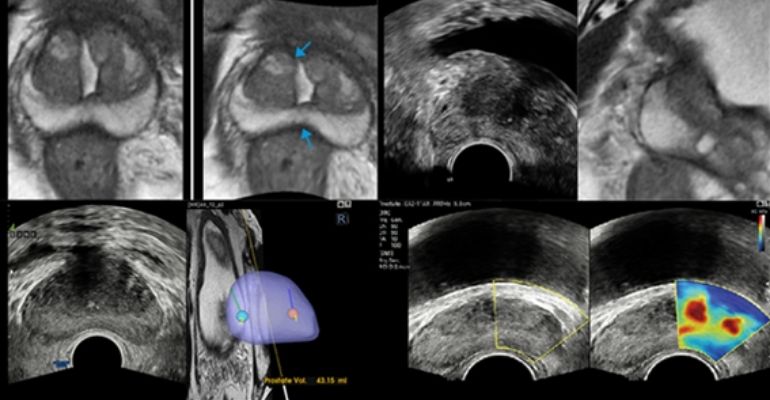

O S-Shearwave Imaging permite uma avaliação não-invasiva da próstata, mamas, tireóide e possíveis lesões a partir de um elastograma, uma espécie de mapeamento em cores dos diversos níveis de rigidez do órgão em estudo. Já o S-Fusion combina imagens de ultrassom com outras modalidades diagnósticas, tais como ressonância magnética e tomografia computadorizada, e trabalha para auxiliar os médicos na realização de biópsias mais precisas na próstata e no fígado, obtidas graças à aplicação modelos matemáticos tridimensionais baseados em inteligência artificial e de sofisticados recursos de navegação e correção de distorções na imagem.